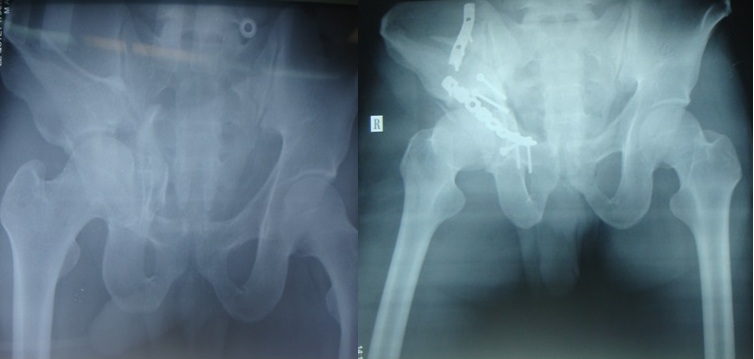

Hình 2: Bệnh nhân Nguyễn Thị T.: kết quả điều trị

Các bệnh nhân sau mổ 2 tháng bắt đầu đi lại dần có nạng và sau 3-4 tháng hầu hết đều đi lại tốt. Có trường hợp sau 1 tháng đã đi lại như bình thường và không đau. Có 1 trường hợp đáng chú ý là bệnh nhân bị vỡ bờ sau ổ cối và có mảnh vỡ kẹt khớp. Bệnh nhân được lấy mảnh vỡ và taí tạo mái ổ cối, sau mổ có triệu chứng đau dọc thần kinh ngồi, đặc biệt là khi vận động thay đổi tư thế. Chúng tôi nghĩ là do trượt thần kinh trên nẹp khi thay đổi tư thế, triệu chứng biến mất sau khi tháo nẹp.